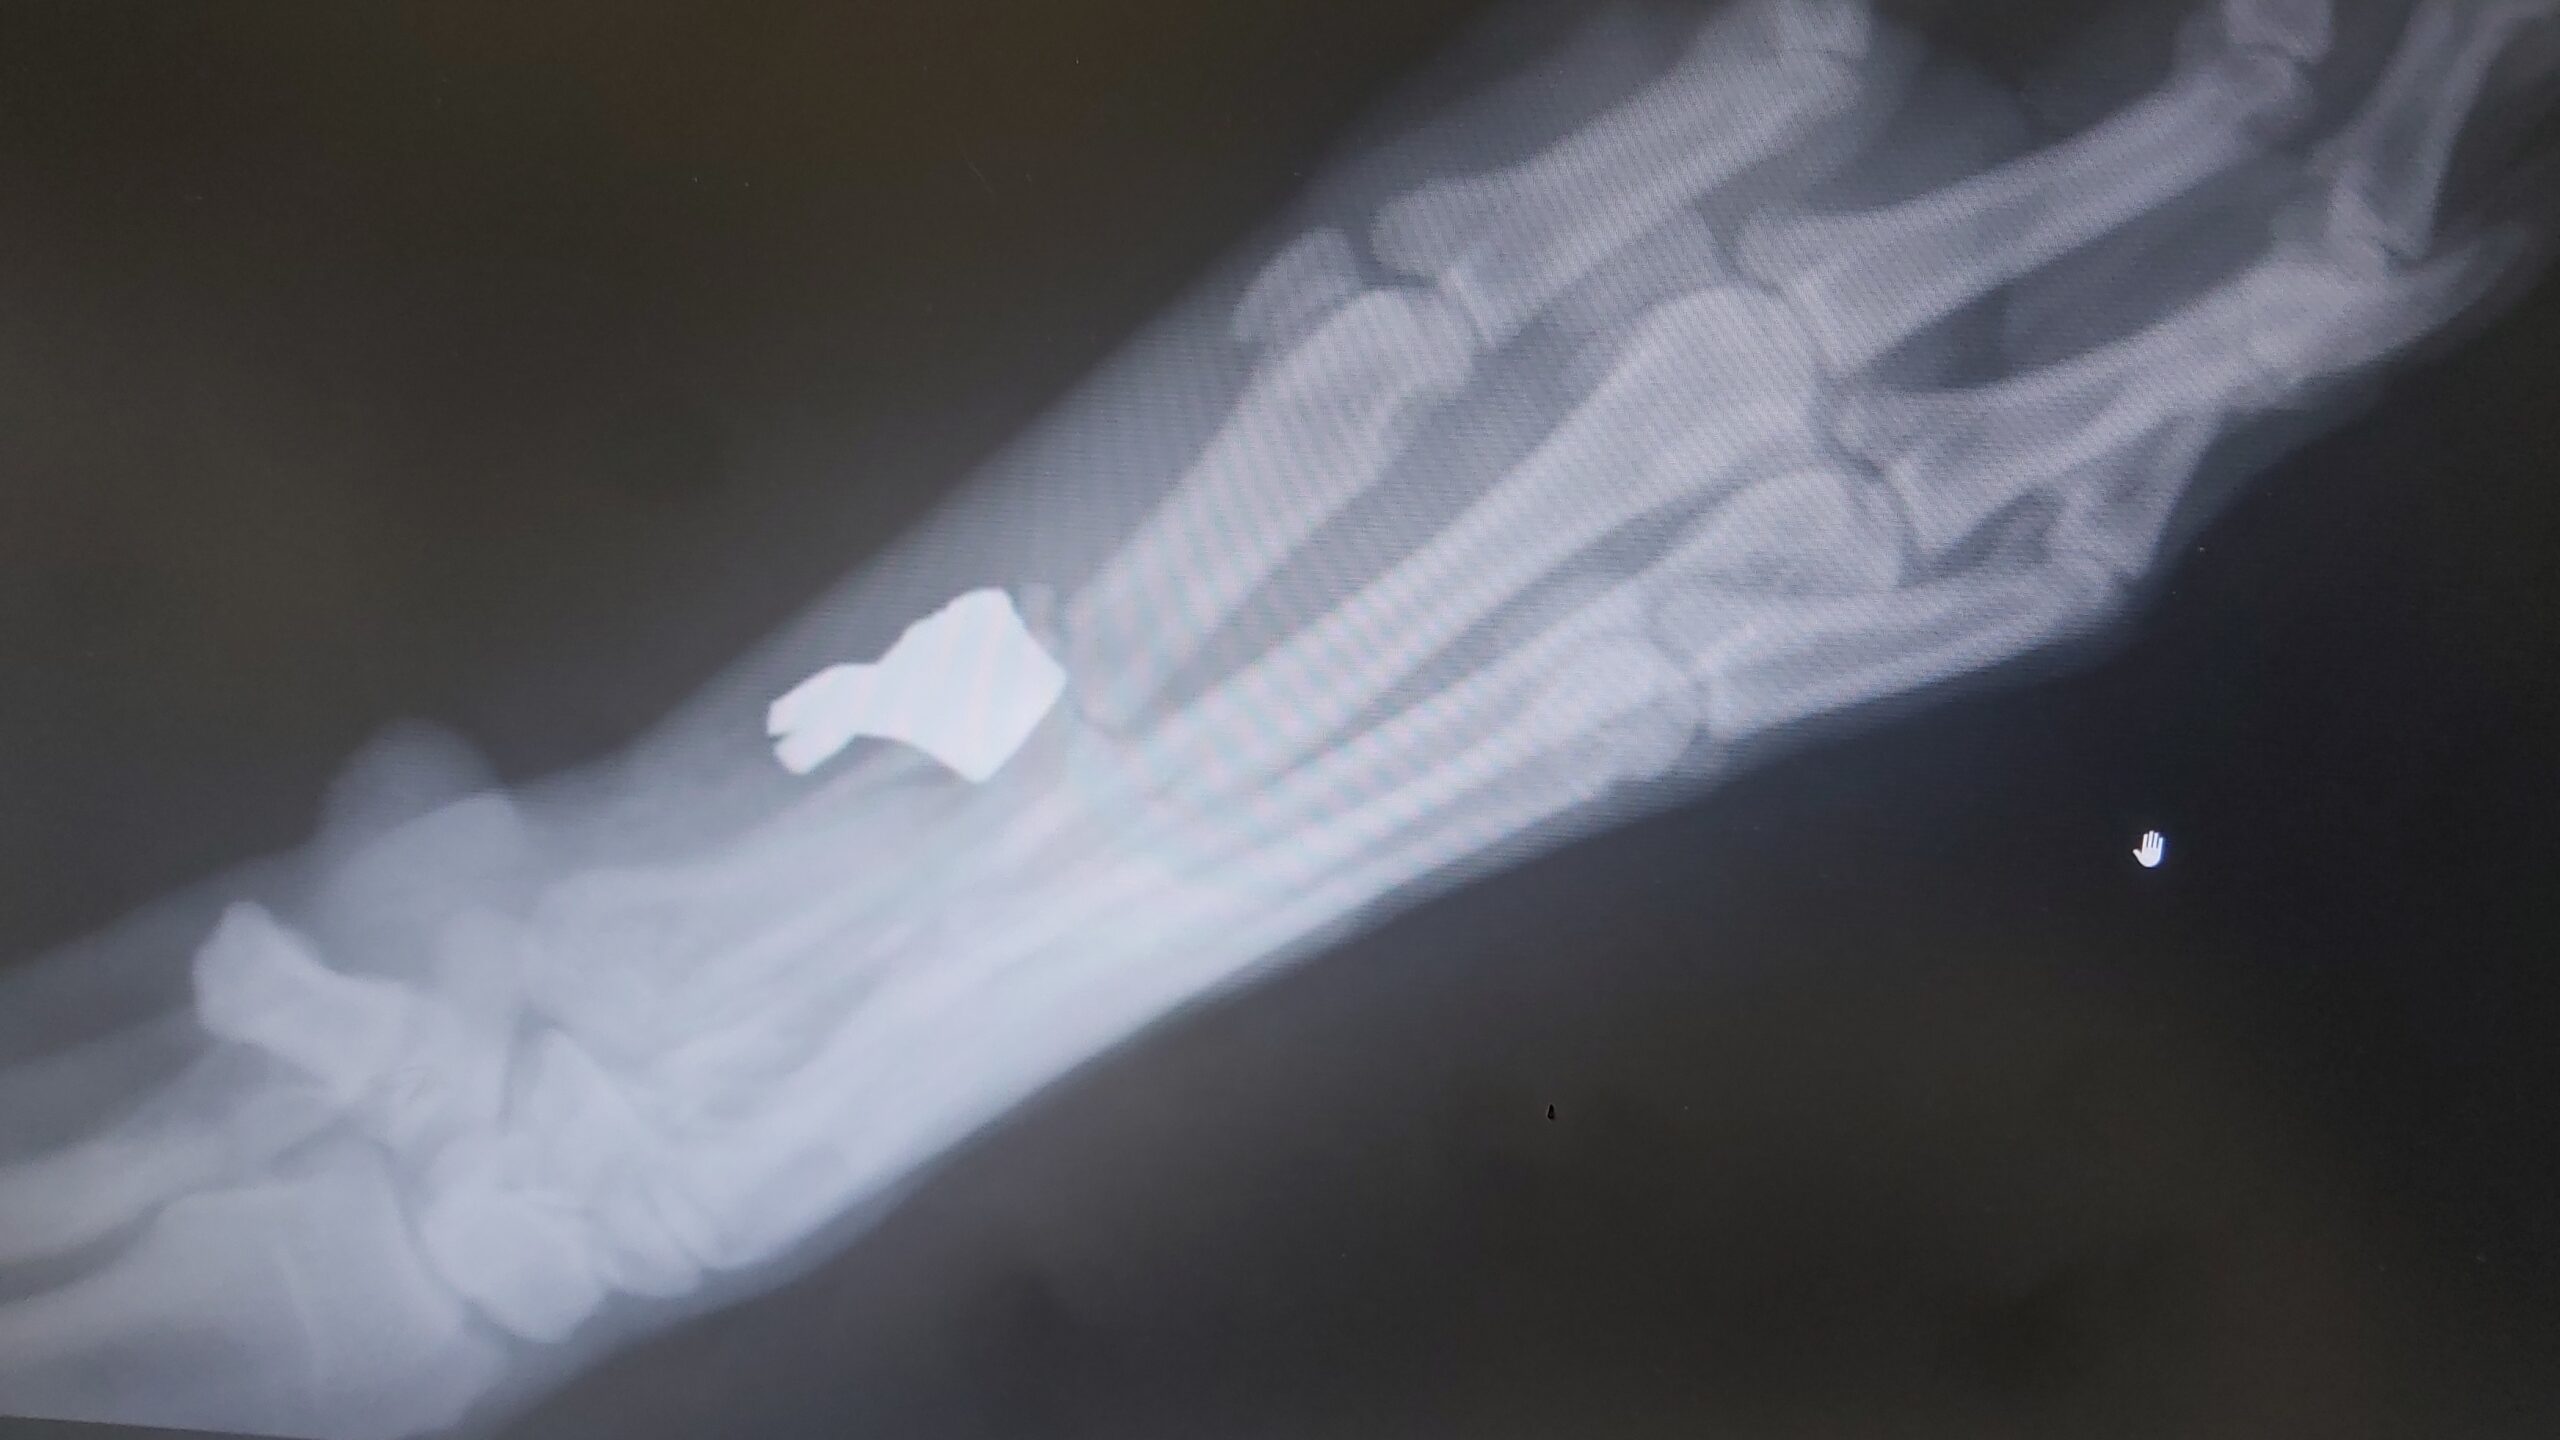

Egy óbudai passzivistánk néhány hónapja megrázó eseményen ment keresztül. Kutyáját, Gizmót az esti sétáltatás közben váratlanul meglőtték. A lábán érte találat. A golyó egy részét kiműtötték, 3 csontja szilánkosra tört, a jobb lábán a főtalppárna nagy része leszakadt, ezt már nem tudták visszavarrni. Az állatorvosi egyetemen még többször megoperálták.

A rehabilitáció a mai napig zajlik, viszont ahhoz, hogy passzivistánk az orvosi kezelést, és a gyógyszereket finanszírozni tudja, ott kellett hagynia lakását és a munkáját, és vissza kellett költöznie szülőfalujába. Nemrég megtalálták Gizmo lábában a golyó másik felét, így vár rá még legalább egy műtét, majd pedig hosszú rehabilitáció.